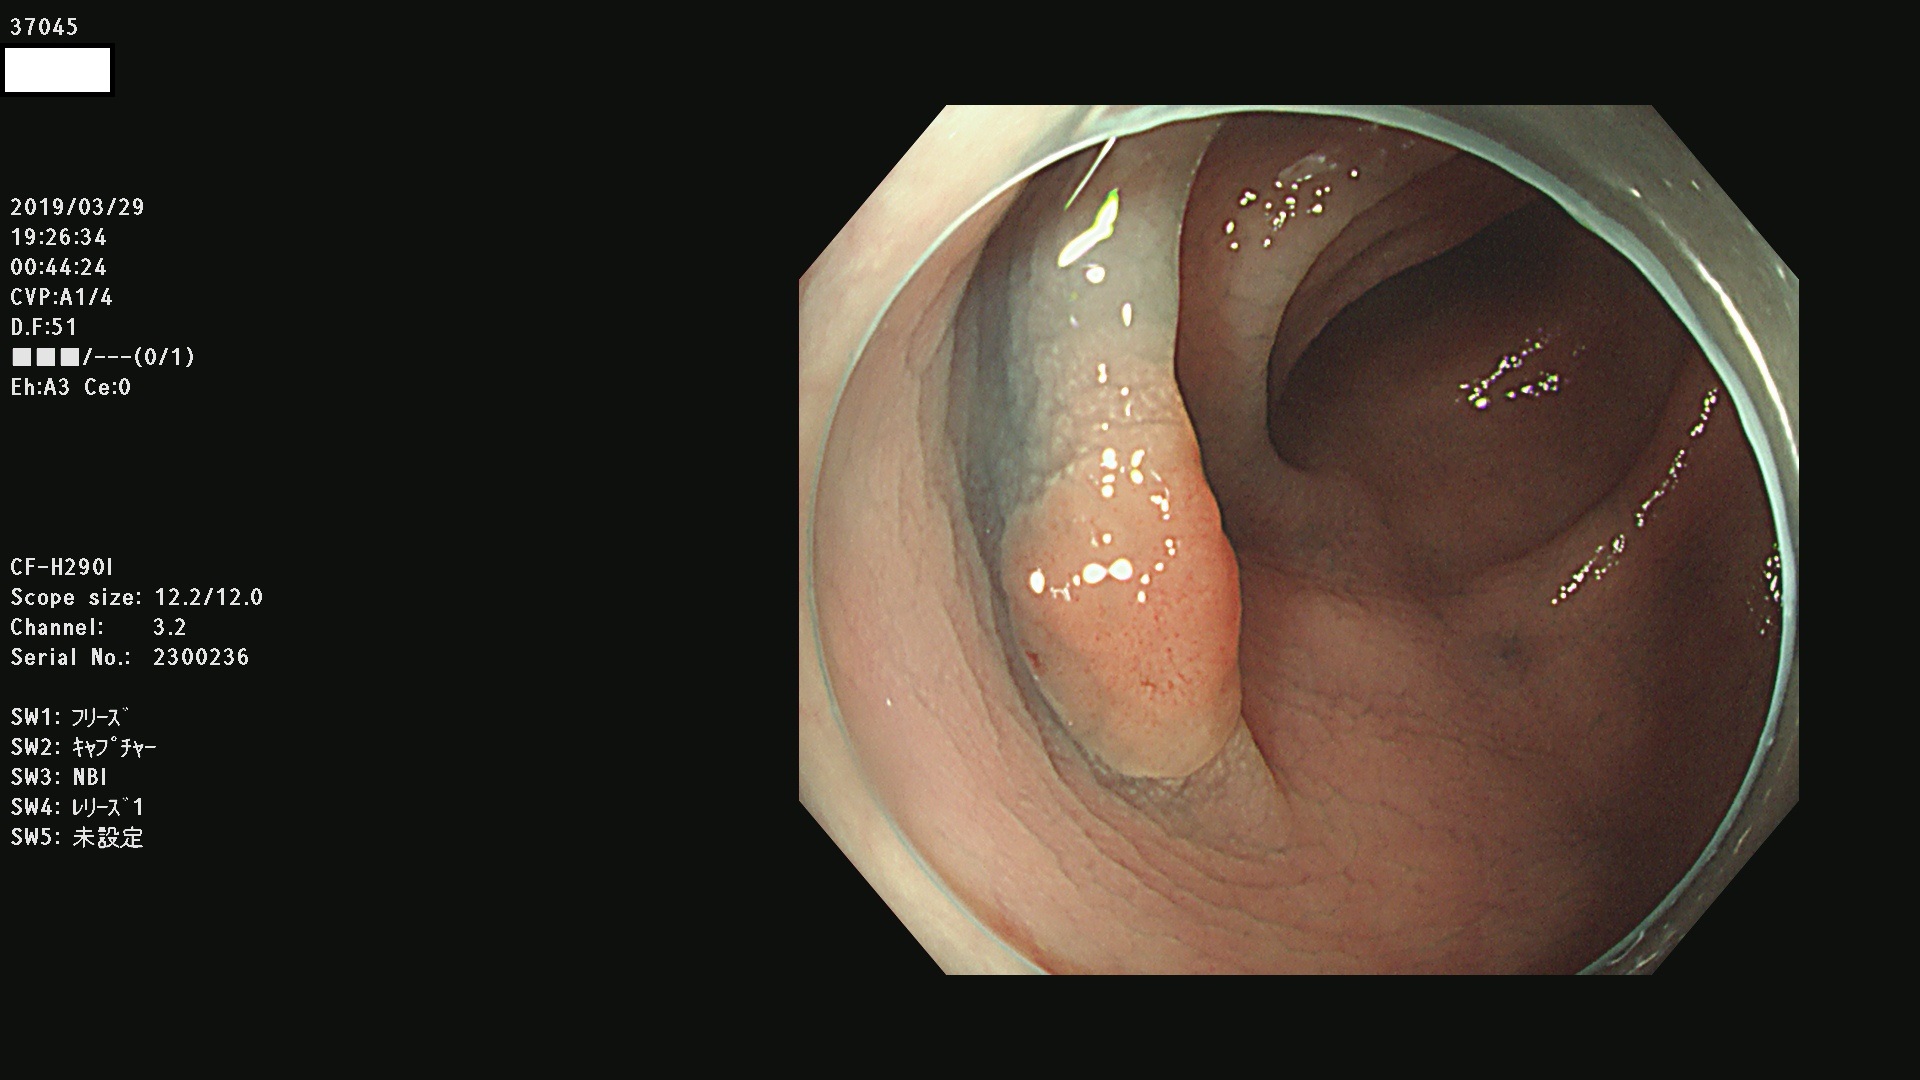

37000 37002 37004 37005 37006(SSAPのみ) 37007 37009 37013 37014 37015 37017(SSAPのみ) 37019 37020 37021 37022 37025 37026 37027 37028 37029 37031 37032 37033 37034 37035 37036 37037 37038 37041 37042 37043 37044 37045 37047 37051 37052 37053(SSAPのみ) 37055 37056 37058 37060 37061 37062 37063 37067 37072 37073 37074 37076 37077 37078 37079 37080 37081 37083 37084 37085(SSAPのみ) 37086 37087 37088 37089 37092 37093 37094 37095 37097 37098 3709

発見困難で危険性の高い平坦型病変(上記100名より抽出)